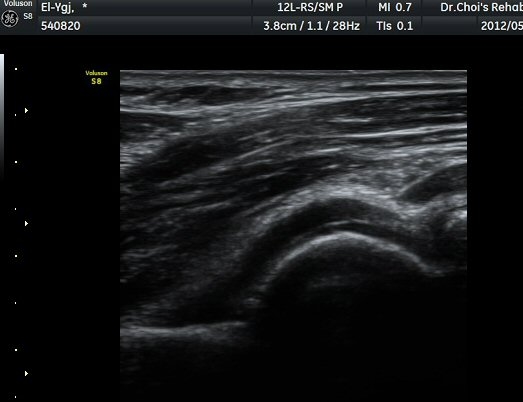

ÁֵοÍ(olecranon fossa) Á¾´Ü¸é°Ë»ç¿Í Ⱦ´Ü¸é°Ë»ç¿¡¼­ ÁÖµÎ¿Í ¼ö¾×Àú·ù¿Í °ø¿¡ÄÚ »À µ¢¾î¸®°¡

°üÂûµÈ´Ù(±×¸² 4, 5, 6).